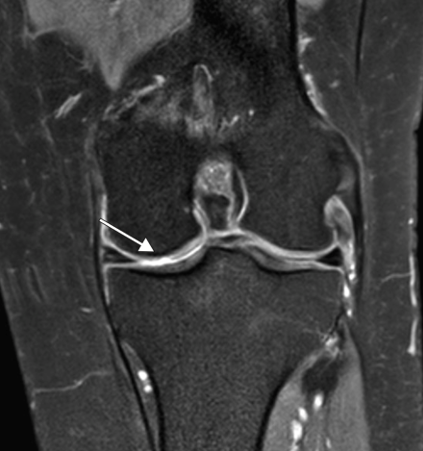

Q. De acuerdo con la imagen, qué signo radiológico identificas y en qué consiste.

Signo del ligamento colateral coronal. Consiste en la pérdida de la disposición oblicua del ligamento, observándolo completo en el un plano coronal, se observa en casos de inestabilidad estática de la rodilla comúnmente secundario a rotura del LCA.